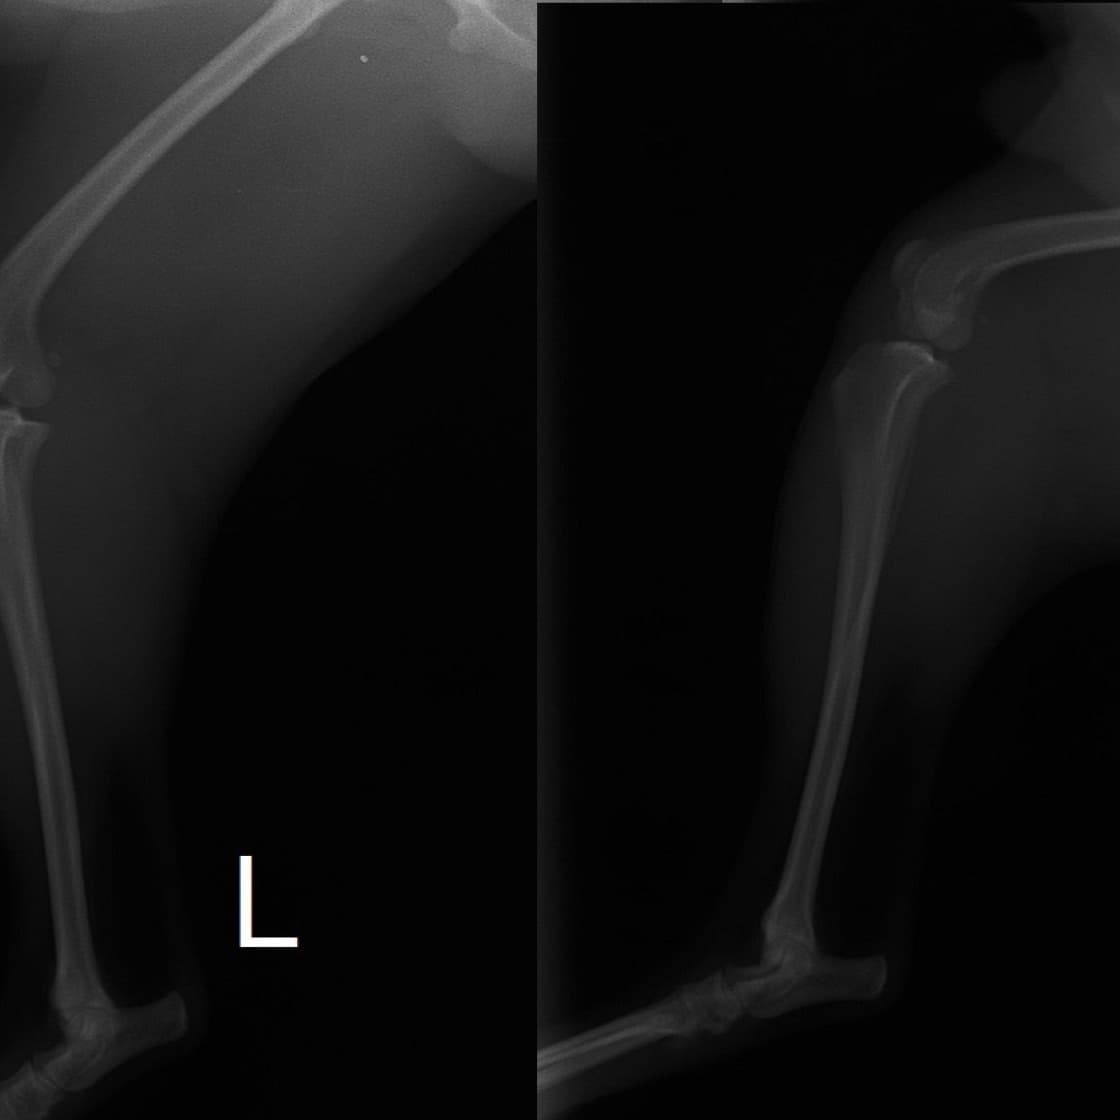

■ 症例22 ポメラニアン 1歳5か月 去勢雄

左後肢の挙上を主訴に来院した。整形学的検査、レントゲン検査より左右の膝蓋骨脱臼(左GradeⅡ〜Ⅲ、右Grade Ⅱ)を認めた。また、脛骨の前方引き出し試験の際に、引き出し兆候は認められないものの、疼痛が認められたため、前十字靭帯の損傷が疑われた。術中における、目視および関節内の操作によって、前十字靭帯の損傷や過伸展といった異常が認められなかったため、膝蓋骨脱臼の整復のみ実施した。手術手技は縫工筋及び内側広筋の解放、脛骨粗面の外側転位、滑車ブロック形造溝術、内外側関節包の縫縮を実施した。本症例は跛行もなく経過良好である。しかし、頸骨高平部の角度(TPA)が 右26.2°、左24.9°であり、解剖学的に前十字靭帯損傷のリスクが高いことから今後の経過に注意が必要である。